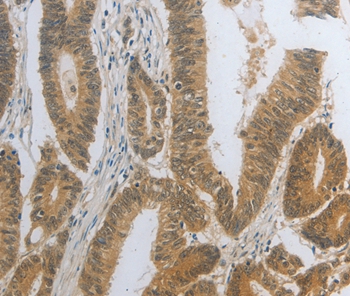

Immunohistochemical analysis of paraffin-embedded Human colon cancer tissue using #35858 at dilution 1/25.